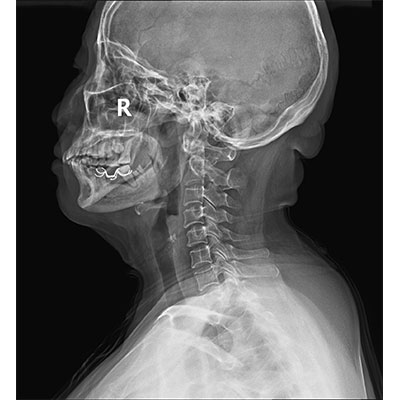

智能化運動(dòng)系統支持一鍵到位,一鍵完成臥位到站立位的智能切換,并自動(dòng)調整適合的SID,平板自主對中校準,準確到達預投照體位。